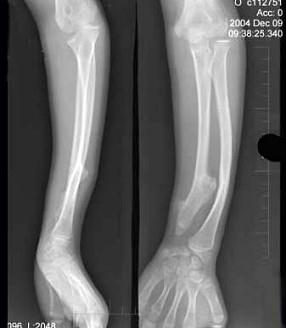

12岁女性患者,左前臂外翻畸形4年,摄片如图所示,最佳的诊断是 ( )A、软骨发育不全B、以上都不是C、马德隆畸形D、先天性干骺端发育不全...

问题 12岁女性患者,左前臂外翻畸形4年,摄片如图所示,最佳的诊断是 ( )

选项 A、软骨发育不全 B、以上都不是 C、马德隆畸形 D、先天性干骺端发育不全 E、奥利病

答案 C